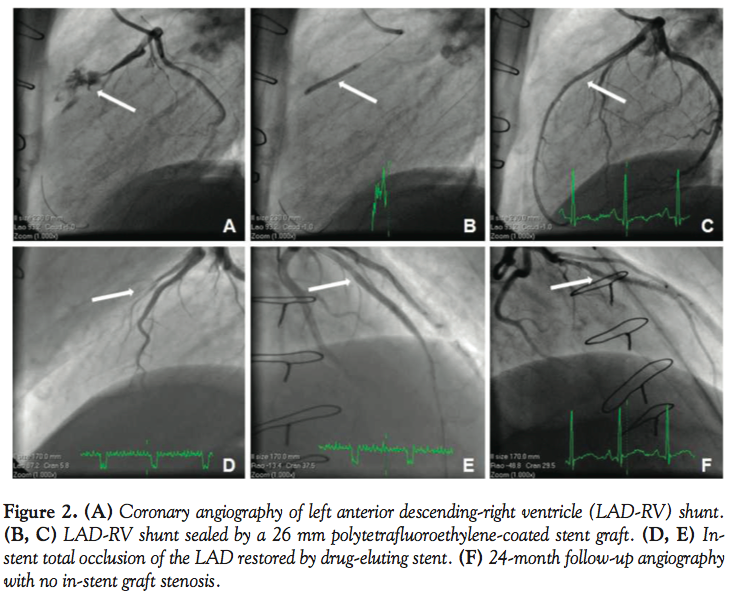

Two days after the index event, subsequent ST elevation +4.0 mV in leads V3-V4 and troponin level of 8.1 ng/mL was observed with no angina symptoms. Transthoracic echocardiography documented akinesia of the left ventricular apical segments, middle segments of anterior wall, and intraventricle septum. Pathological blood flow along the left anterior descending (LAD) directed to the right chamber was also observed (Figures 1A and 1B). Diagnostic angiography identified a fistula from the left coronary artery (LCA) descending to the right ventricle (LAD-RV) with a steal phenomenon and TIMI 2 flow (Figure 2A). LAD-RV shunt was successfully sealed by a 26 mm polytetrafluoroethylene-coated stent graft. Procedure effect was optimal, with TIMI 3 flow (Figures 2B and 2C). The patient was discharged on the 25th day of hospitalization with no clinical evidence of RV failure or angina symptoms.

Four months after index event, the patient was again admitted to our emergency department with recurrent angina symptoms. An urgent coronary angiography revealed an in-stent total occlusion of the LAD, which was promptly restored with implantation of a 3.0 x 32 mm paclitaxel-eluting stent (Figures 2D and 2E). No significant restenosis was observed at 24-month follow-up angiography (Figure 2F).